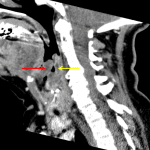

- Extensive edema involving the supraglottic larynx including edematous appearance of the epiglottis and aryepiglottic folds

- Peripherally enhancing fluid collection in the posterior wall of the hypopharynx may represent a small abscess

- Narrowing of the supraglottic airway, which remains patent

- Epiglottitis

- Possible small abscess along the posterior wall of the hypopharynx

Marked edema of the supraglottic larynx, notably with edematous epiglottis and aryepiglottic folds, consistent with acute epiglottitis and laryngitis. Recommend ENT consultation.

The supraglottic airway is narrowed, but remains patent.

More discrete peripherally enhancing collection measuring 10 x 5 mm along the posterior wall of the hypopharynx is concerning for a small abscess.